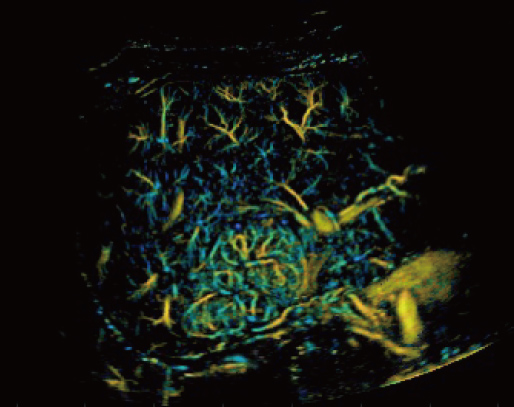

Resona A20 supports clinicians in cutting-edge clinical research. Super

Resolution CEUS (SR CEUS) reveals blood perfusion details at the micron

level, aiding clinicians in the exploration of early microcirculatory

changes in lesions. Additionally, STVi shear wave viscoelastography, a

Powered by the AIT platform, the Resona A20 delivers an all-in-one

integrated solution for super-resolution imaging, a capability

previously difficult to achieve. SR CEUS reveals the intricate

microcirculation details of lesions at the micron level, aiding in

microcirculatory perfusion studies in oncology.

Microvascular detection capabilities

Focal Nodular Hyperplasia | Density Map

Focal Nodular Hyperplasia | Direction Map

Focal Nodular Hyperplasia | Velocity Map